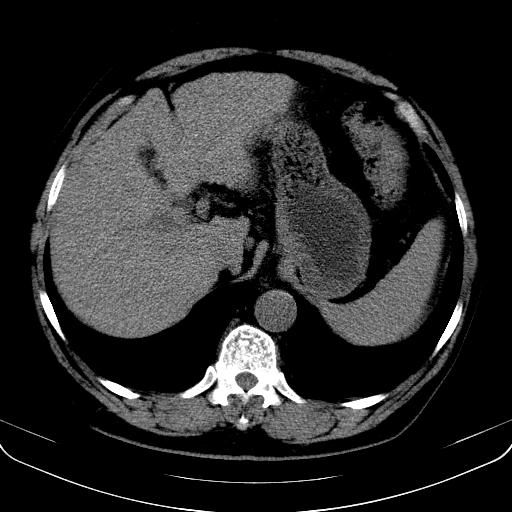

以下是引用jia119在2008-3-5 13:31:00的发言:[br]肝内多发片状低密度影,密度不均,我还是考虑肝ca可能,另肝内小囊肿,胆囊增大。

以下是引用形影不离在2008-3-5 12:18:00的发言:[br]肝硬化伴门脉高压征,肝内占位待排,增强再说.

以下是引用随光逐影在2008-3-5 21:11:00的发言:[br]肝硬化伴门脉高压(食管下段静脉曲张),肝癌不排除。建议:行ct增强扫描检查。

以下是引用同在2008-3-5 13:56:00的发言:[br]考虑肝癌可能性大,胆囊增大.